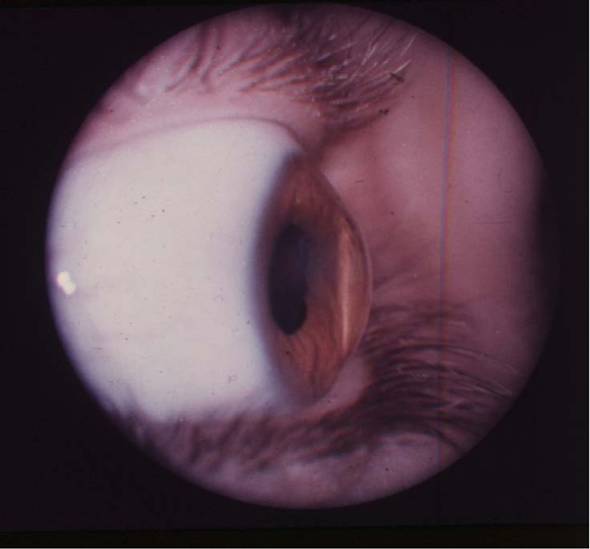

рис. 9.2.8), отмечая инъекционной иглой, смоченной 1% спиртовым раствором бриллиантовой зелени (см. рис. 9.2.9). Специальным отметчиком отмечают оптическую зону диаметром 6,0 мм (см. рис. 9.2.10). Сильный и слабый меридианы рефракции роговицы отмечают в области лимба перед подачей больного в операционную 1% спиртовым раствором бриллиантовой зелени по системе «Табо».С помощью отметчика роговицы (рис. 11.2.1) отмечают главные меридианы роговицы, затем определяют сектор сильного меридиана при простом миопическом астигматизме и по линии отметки оптической зоны производят насечку длиной до 1,0 мм на глубину 0,2 мм алмазным ножом с дозированной подачей лезвия, такую же насечку делают и в противоположном секторе (рис. 11.2.2) На глубине насечки специальным роговичным шпателем (рис. 11.2.3) делают расслаивание роговицы по линии отметки центральной зоны на % ее окружности. Точно такое же расслаивание проводят и в противоположном секторе. В сформированные тоннели микропинцетом вводят приготовленные заранее лентовидные трансплантаты с несколько заостренными краями и расправляют микрошпателем (рис. 11.2.4). Подсушенные трансплантаты имеют упругую консистенцию и легко вводятся в тоннели (рис. 11.2.5).

Рис. 2.2.9. Кератоконус IV степени

Рис. 2.2.10. Кератоконус IV степени, снимок сбоку